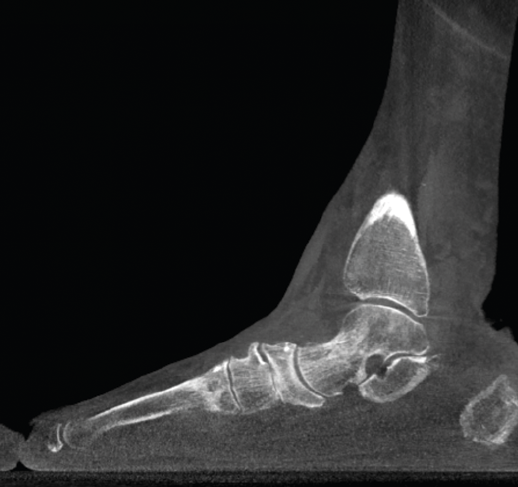

Figura 2. Severo pie plano valgo bilateral con pinzamiento fibular.

- Pie plano valgo del adulto. Permite la valoración de la articulación subtalar, el valgo del retropié y la inestabilidad de la columna medial (Figuras 2 y 3).